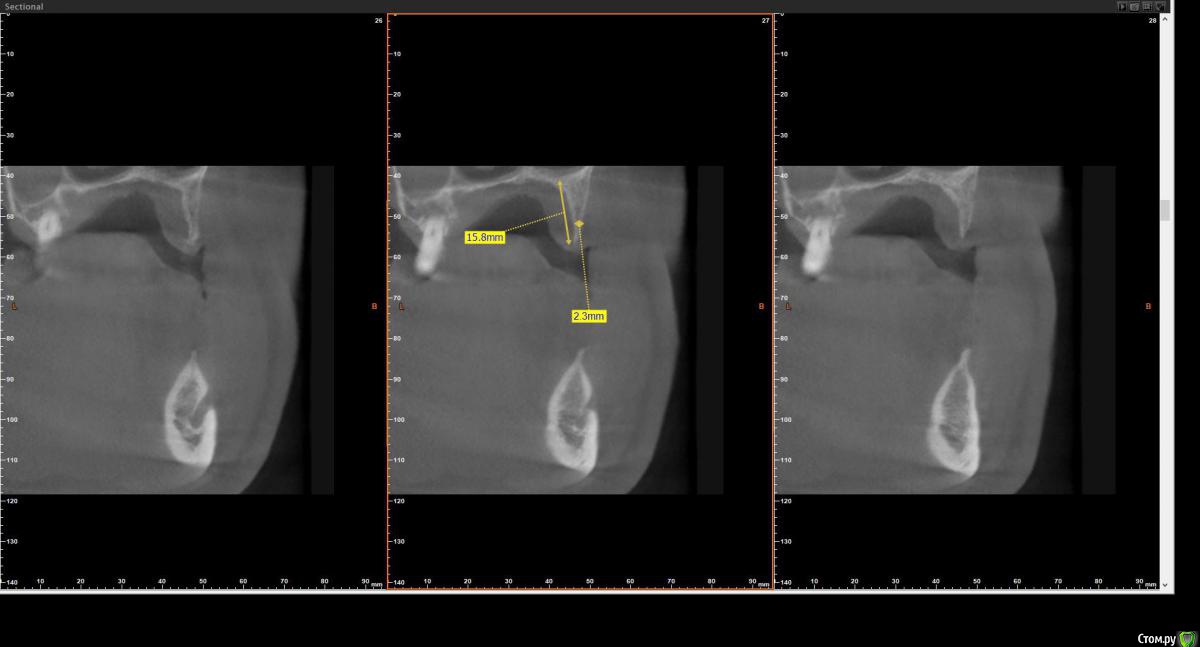

Grigomir Опубликовано 2 августа, 2018 Поделиться Опубликовано 2 августа, 2018 Уважаемые коллеги! Хочется установить имплант на вч. Как бы вы поступили в данной ситуации? Ссылка на комментарий

hogsmeed Опубликовано 2 августа, 2018 Поделиться Опубликовано 2 августа, 2018 Расщепление гребня и НКР ? Ссылка на комментарий

Bier Опубликовано 3 августа, 2018 Поделиться Опубликовано 3 августа, 2018 Сделать НКР, потом поставить имплантат. Атрофия класса "С" 1 Ссылка на комментарий